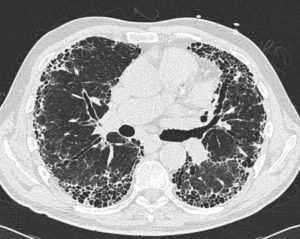

- Компьютерная томография – на снимках заметен характер изменений в легких, объемы и структура разрастающейся ткани.

В настоящее время компьютерная томография легких является одной из самых точных методик диагностики идиопатического легочного фиброза.

- Компьютерная томография высокого разрешения (КТВР, МСКТ КТВР) это специальное рентгенографическое исследование. Достоверность диагноза ИЛФ при применении использовании этого метода составляет 90%. На снимках отчетливо видны все фиброзные изменения легких вызванных ИЛФ